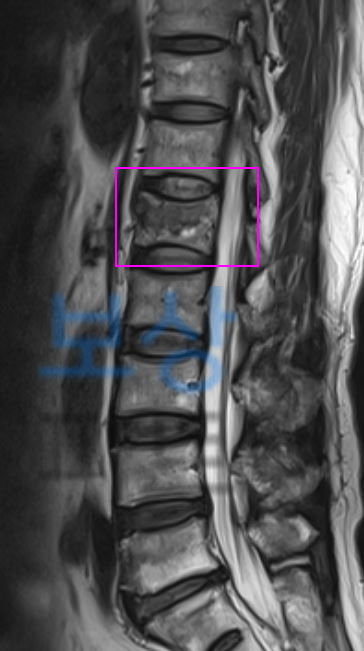

보상파트너로 문의해주셨던 서울시 거주 박@@님 또한 무거운 책을 드시다가 허리를 삐끗하셨다고 했는데요, 계속된 통증에 병원에 내원하여 Mri 등 정밀 검사를 받으셨고 진단 결과

L1 척추 요추압박골절

S32020 진단받으셨습니다. 박@@님은 수상일로부터 약 8주간 TLSO 허리보조기 착용하며 비수술 보존치료 진행하셨는데요, 장해보험금 청구를 위해서는

영상CD 및 영상판독지를 보면 Acute compression fracture in L1 **급성 요추압박골절 **확인됩니다. 보상파트너는 보험사도 인정할 공신력있는 상급병원 전문의로부터 후유장해 평가 받았고